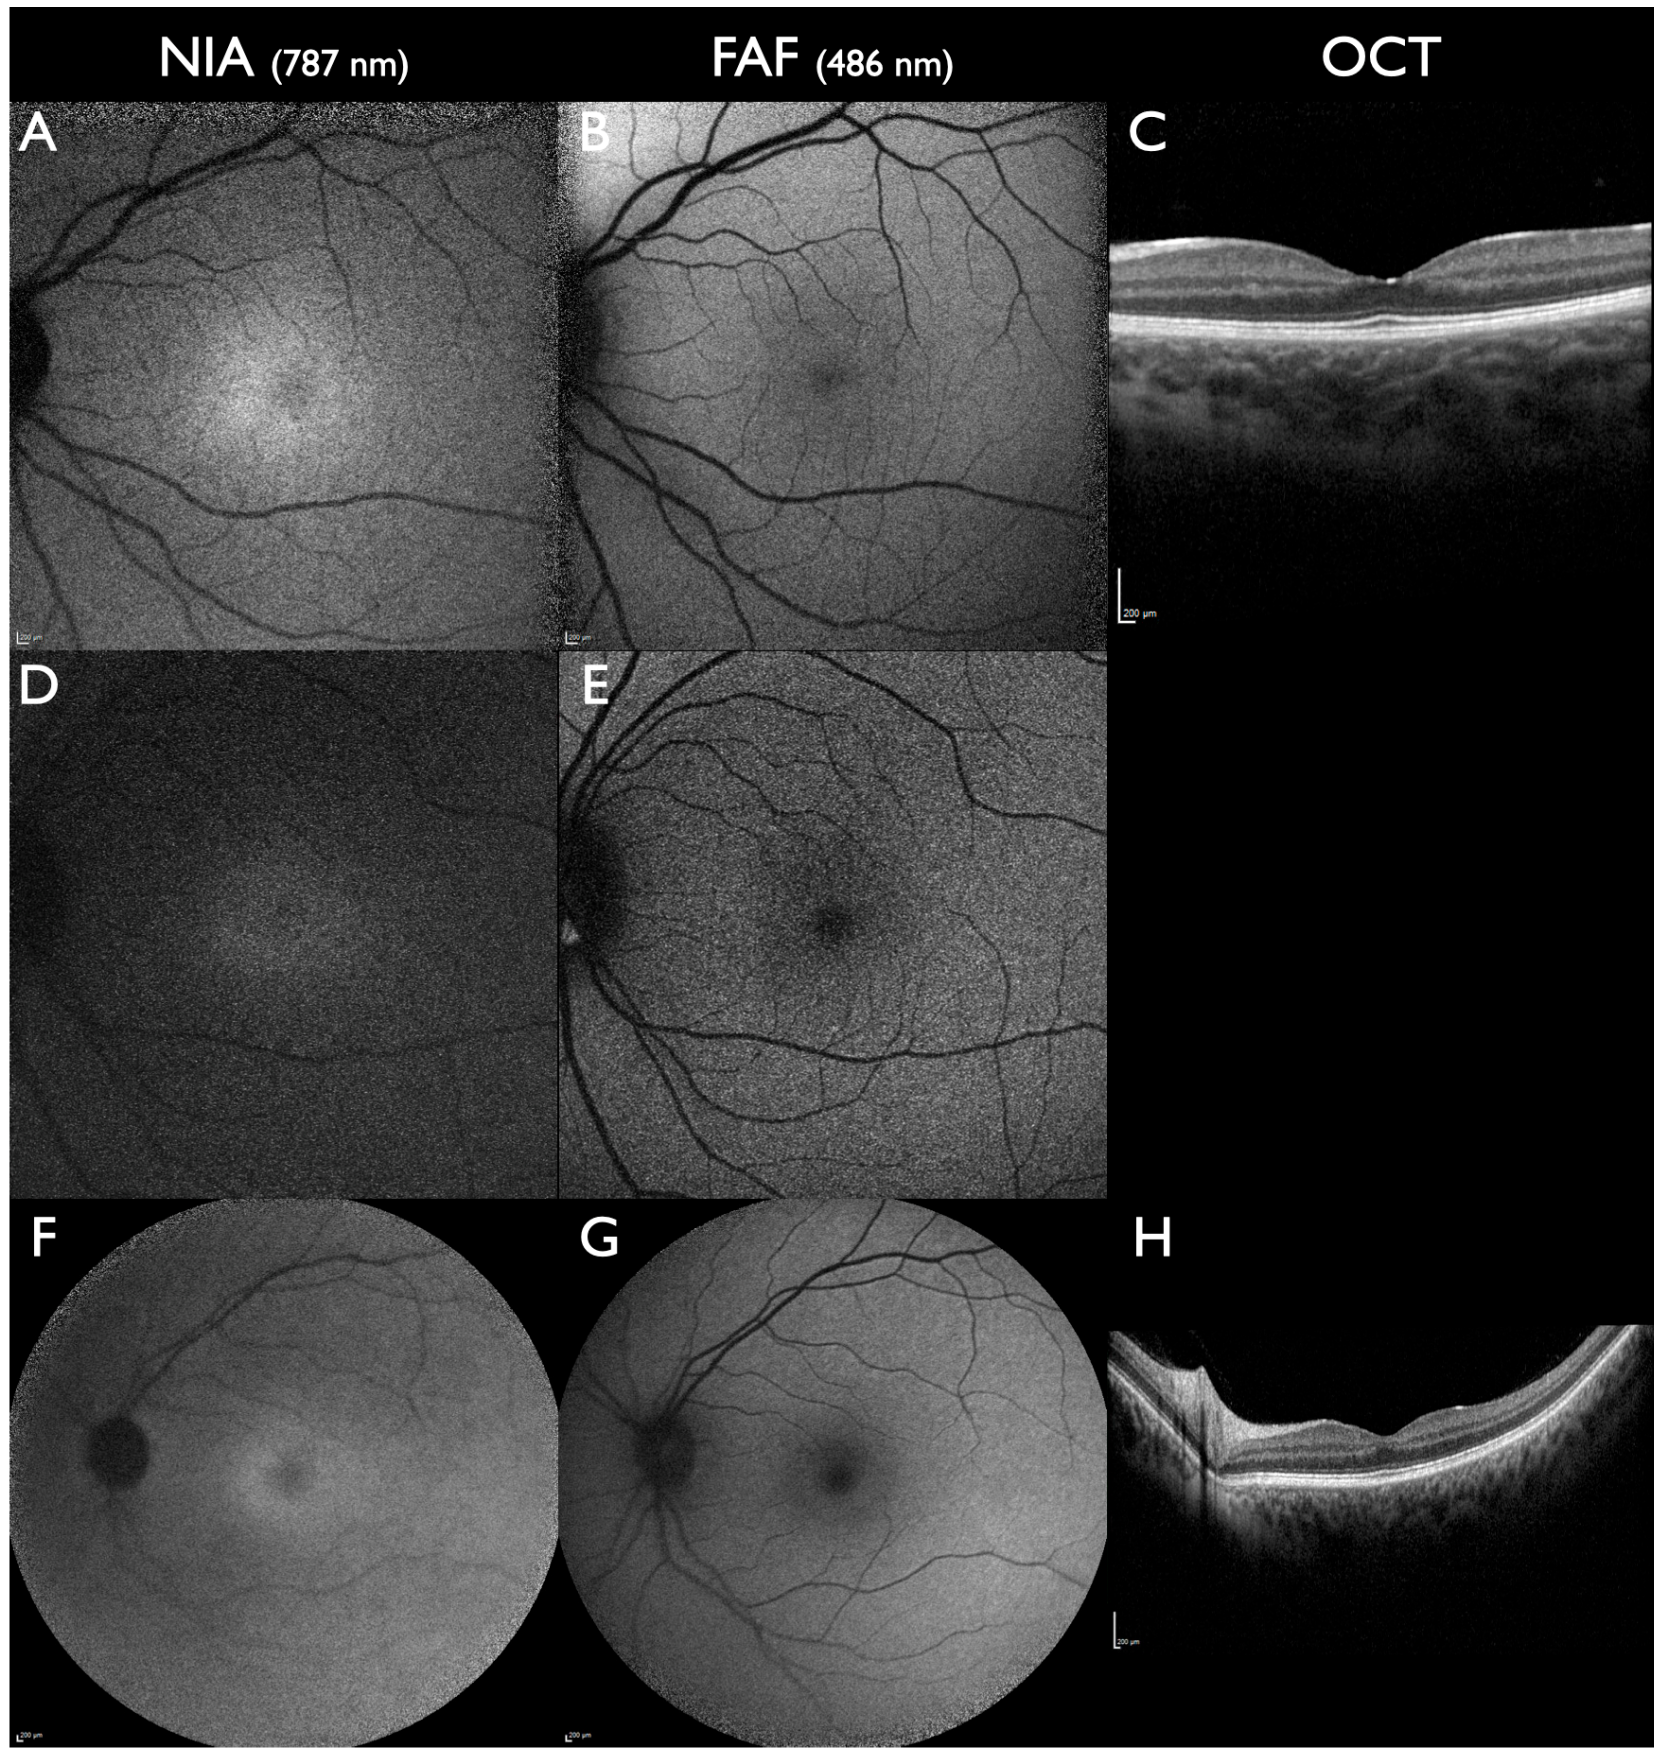

| Preclinical Best macular dystrophy | Subfoveal reduced intensity [29,63] | Normal | Normal | Only detectable by NIA |

| Best macular dystrophy | -Lesions with increased or reduced intensity -Areas of reduced intensity increasing during progression -Subfoveal preserved NIA intensity associated with better VA [62] | -Lesions with increased or reduced intensity -Areas of reduced intensity increasing during progression | -Subretinal fluid and/or subretinal material -Atrophy of outer retinal layers (EZ line) and RPE in late stages | Reduced NIA intensity precedes reduced FAF intensity [62] |

| Autosomal recessive Bestrophinopathy | -Areas of variably increased or reduced intensity -Peripapillary sparing | -Areas of variably increased or reduced intensity -Peripapillary sparing | -Subretinal material, subretinal fluid -Atrophy of outer retinal layers (EZ line) and RPE in late stages | Subfoveal reduced NIA intensity corresponds to vascular rarefication and CME [64] |

| Retinitis pigmentosa | -Pericentral ring of increased intensity corresponding to the end of the EZ line in OCT -Marked intensity loss peripherally to the ring in areas with preserved or absent RPE | -Pericentral ring of increased intensity corresponding to the end of the EZ line in OCT -Preserved intensity adjacent to the ring and marked loss further peripherally | Variable: centrally preserved or reduced outer retinal layers (EZ line), towards the periphery loss of outer retinal layers and RPE, CME in about 50% of cases | -Ring of increased intensity in NIA more centrally compared to FAF [81,82] -Absent NIA intensity corresponds to vascular alterations in OCTA [86] |

| Choroideremia | -Early-onset wide-spread reduction in intensity -Small areas of preserved intensity correlate to unspeckled area of FAF intensity | -Multiple irregular areas of reduced intensity, -Central area of preserved intensity surrounded by an area with speckled loss of intensity | Variable: centrally preserved or reduced outer retinal layers (EZ line) towards the periphery; increasing areas of loss of outer retinal layers and RPE | -Area of preserved NIA smaller compared to FAF [90] -Subfoveal preserved NIA correlates with better VA [89,90] |